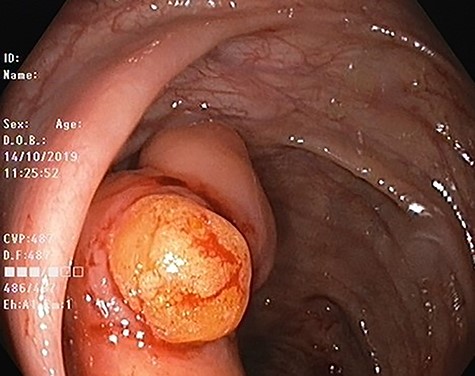

Our patient is 56-year-old female, a known case of locally advanced breast carcinoma. She was initially managed by chemotherapy followed by modified radical mastectomy then adjuvant radiotherapy and chemotherapy. The patient gave a positive family history of colon cancer; therefore, genetic testing for adenomatous polyposis coli (APC) mutation and surveillance colonoscopy were recommended by genetic counselor. The APC gene mutation came to be positive and as part of the work up for her primary disease, computed tomography (CT) scan of the abdomen performed and showed evidence of 4 cm intraluminal lesion in the ascending colon suggestive of lipoma without bowel obstruction (Fig. 1). As a result of these findings, colonoscopy was performed and it revealed a large smooth intraluminal subepithelial lesion in the ascending colon occupying one third of the lumen circumference (Fig. 2). With the use of biopsy forceps, indentation of the tumor can be seen, which is as known as “pillow sign” and once a biopsy taken, a fatty yellowish material was seen protruding from the biopsy site suggestive of lipoma (Fig. 3). Histopathological examination showed multiple fragment of normal colonic mucosa and fragments of mature adipose tissue consistent with lipoma (Fig. 4, black arrows). Clinically, the patient denied history of abdominal pain, rectal bleeding, changes in her bowel habit and intestinal obstruction symptoms. She denied any personal history of malignancy or lipoma. On physical examination, there was no evidence of any lipomas in particular her scalp, limbs or trunk. Although she has no gastrointestinal symptoms attributed to the lipoma, given that it is large in size and she is in clinical and radiological remission, we referred her for the opinion of colorectal surgery.

Colonic lipoma after biopsy showing typical yellowish adispose tissue.